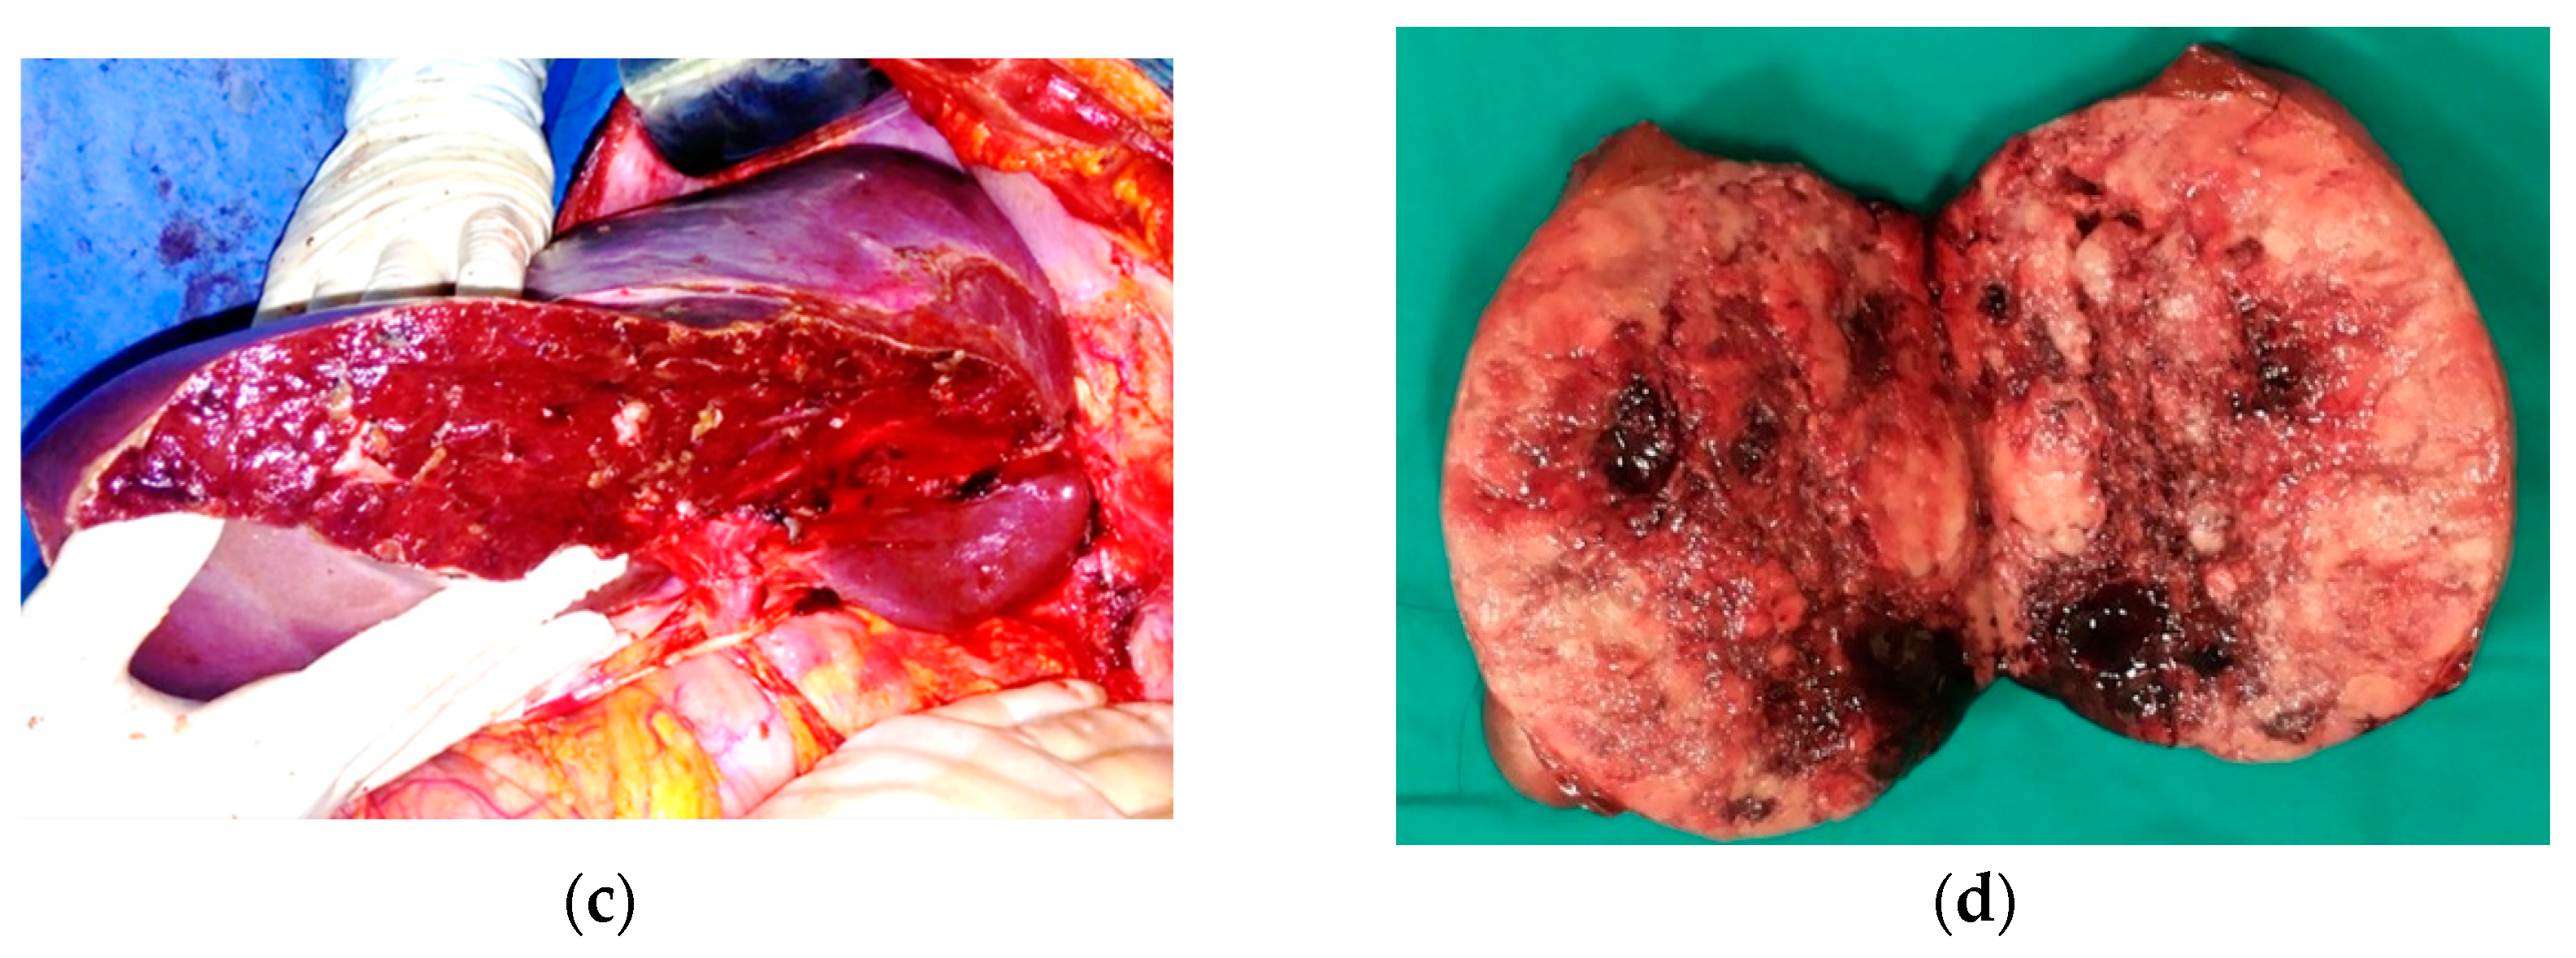

Seven weeks after the first resection, we performed the second stage of the debulking procedure, which consisted of an intraoperative ultrasound-guided right posterior sectionectomy extended to segments 5 and 8, along with the resection of the invaded right hepatic vein, removing the large confluenced metastases located in the right hemiliver (Figure 6) with a portocaval shunt using Gore-Tex graft interposition to decrease post-resectional portal hypertension.

Figure 6.

Second-stage surgery. Aspect of the liver: (a) prior to second resection; (b) after resection; (c,d) resected specimen.

The operative time was 480 min, and blood loss was 2700 mL, necessitating a five-unit blood transfusion. The postoperative course was relatively uneventful, with the exception of fever on POD 11 (remitted by antibiotherapy) and right pleural effusion requiring drainage on POD 12. The patient was discharged on POD 19. The CT scan performed before discharge showed few remaining small liver metastases (the largest had a diameter of 26 mm) and asymptomatic small fluid accumulation on the liver cut surface (treated conservatively) (Figure 7).

Figure 7.

Contrast-enhanced postresection CT image showing (a) a few remaining small liver metastases (the largest of which had a diameter of 26/17 mm) (b) and an asymptomatic collection on the liver resection surface.